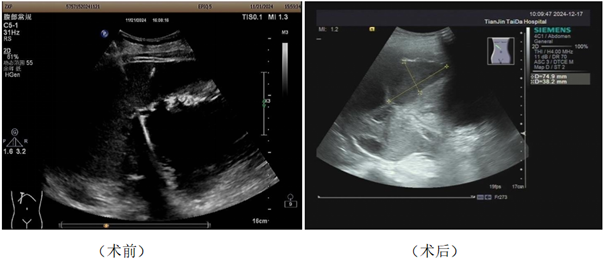

近日,一位 82 岁的男性,无明显诱因地出现了右上腹间断性钝痛,并伴有腰背部疼痛。2024 年 11 月 11 日,外院超声检查提示其患有肝多发囊肿、胆囊炎以及胆囊多发结石。11 月 19 日,外院腹部 CT 进一步提示存在肝脓肿的可能性,化验结果也显示白细胞、胆红素、谷丙及谷草转氨酶均升高。经过对症处理后,症状虽有所缓解,为寻求进一步诊治,患者到泰达医院就诊,并以“肝脓肿?多发性肝囊肿?胆囊结石伴胆囊炎”的诊断收住院。

这位高龄患者同时还患有高血压、糖尿病、脑梗等多种基础疾病。如此复杂的病情,使得患者无法耐受手术治疗,而且长时间的抗生素治疗还可能导致肝肾功能不全。然而,患者连续多日高烧不退,情况十分危急。关键时刻,医院迅速组织多学科会诊,经过严谨讨论,决定为患者实施超声引导下经皮经肝肝脓肿穿刺置管引流术。

术后仅第三天,患者的右上腹疼痛及不适症状就得到了明显缓解。数日后,又进行了第二个肝脓肿穿刺引流术。随后,引流液由脓性成功转为清亮液体,患者进食后未再出现腹痛、腹胀等症状。化验结果显示,白细胞、中性粒细胞均已恢复正常,患者一般状态良好,只需定期复查即可。